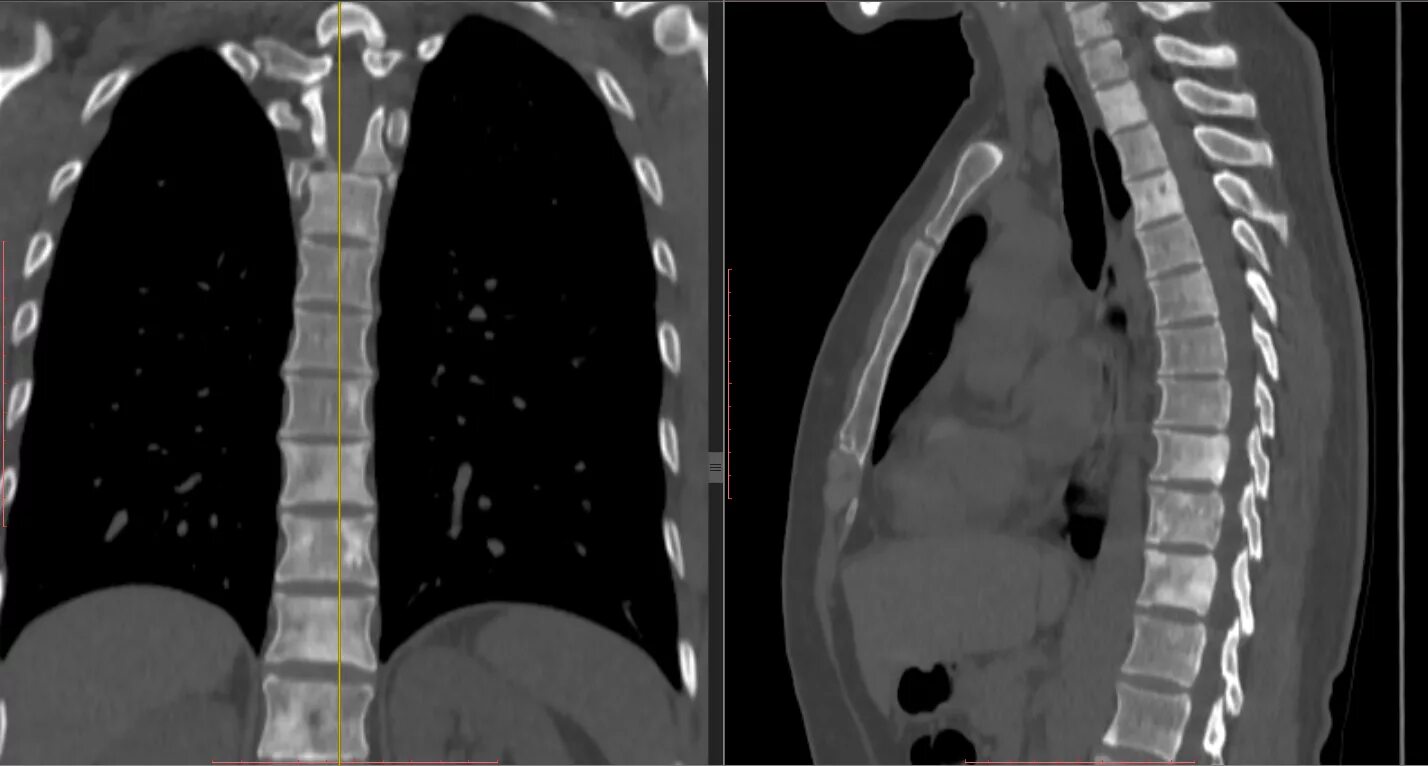

Можно вылечить метастазы кости